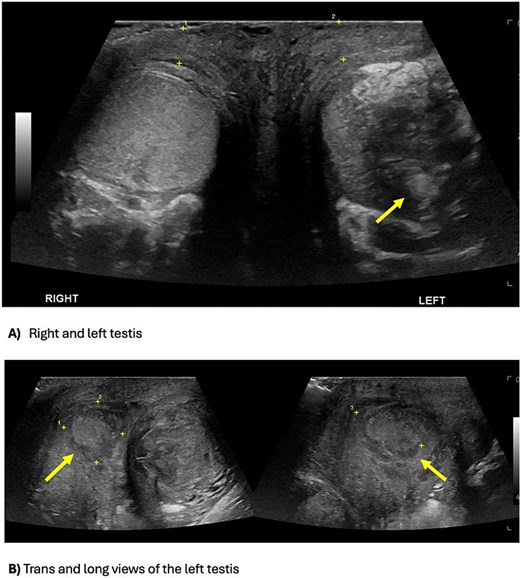

Inflammatory markers were mildly elevated—white cell count 12 × 109/l, C-reactive protein 30 mg/l. Scrotal ultrasound demonstrated a left intratesticular abscess, ruptured tunica albuginea, and suspected ischaemia (Fig. 1). Ordered due to recurrent AEO, a computed tomographic (CT) intravenous pyelogram revealed a fistula between the sigmoid colon and dome of the bladder, secondary to diverticular disease (Fig. 2). Urine cultures from his last admission for epididymo-orchitis grew multi-resistant Escheria coli and Enterococcus faecium.

Scrotal ultrasound demonstrating an ill-defined and heterogeneous left testis with a central hypoechoic part of decreased vascularity suggestive of an abscess, versus the homogenous and normal vascularity right testis (A). The testicular abscess extends medially through the tunica albuginea, causing a scrotal wall abscess (B).